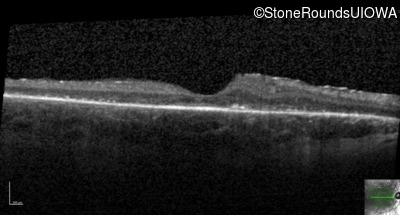

This 21 year old man first had difficulty seeing the blackboard in the 5th grade. Two years later he began having difficulty seeing in dim light. In high school he was approximately 50 pounds overweight, but was able to lose that weight with a strict diet.

| Bardet Biedl Syndrome | BBS1 | Met390Arg ATG>AGG | Arg277Lys AG(G)>AA(G) | AR |